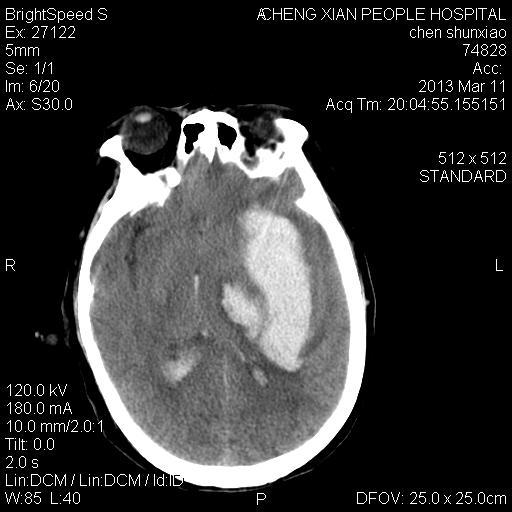

患者陈++,男,71岁。因“昏迷四小时,伴右侧肢体活动受限”以“脑出血”收住院。发病后12小时用“改良立体定向-软通道微创介入新技术治疗脑出血”。术后24小时颅内出血大部被清除,患者神志清晰。右侧肢体肌力0级。

患者陈++,男,71岁。因“昏迷四小时,伴右侧肢体活动受限”以“脑出血”收住院。发病后12小时用“改良立体定向-软通道微创介入新技术治疗脑出血”。术后24小时颅内出血大部被清除,患者神志清晰。右侧肢体肌力0级。